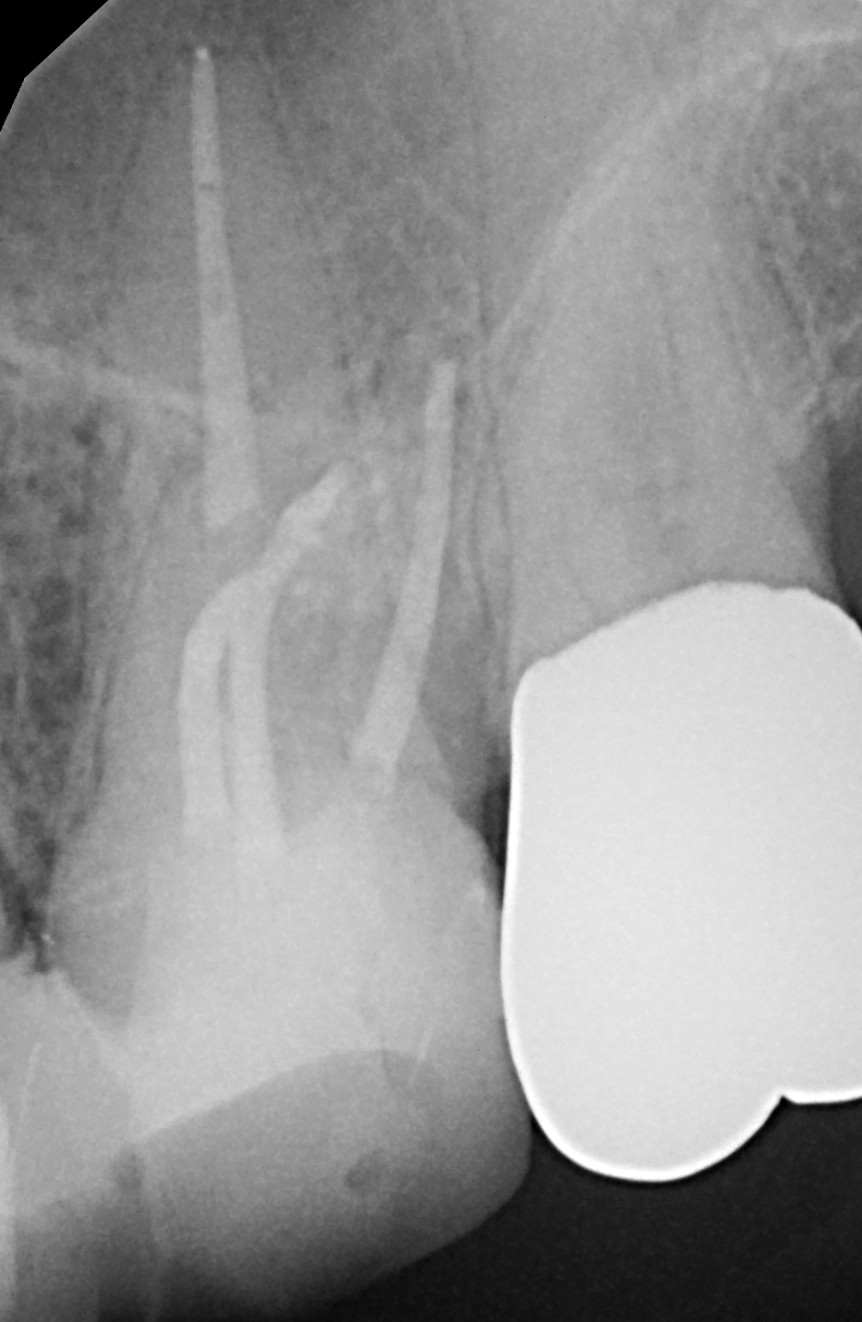

Die Abbildung 54 zeigt das Kanalsystem unmittelbar vor der Wurzelkanalfüllung, die Abbildung 55 nach der vertikalen Kondensation des Wurzelfüllmaterials. Um eine weitere Schwächung des Wurzeldentins zu vermeiden, favorisieren wir eine passive Stiftinsertion ohne weitere Stiftbettpräparation. Auch bzw. insbesondere, wenn ein Zahn mit einem Stift-Stumpf-Aufbau versehen werden soll, sollte ein zusätzlicher Hartgewebsverlust möglichst vermieden werden, der die Prognose des Zahnes zusätzlich verschlechtern würde [17,33,88,93]. Die Schlussfolgerung aus den angeführten Studien ist, auf eine Stiftbohrung zu verzichten, wenn ein Wurzelkanal im koronalen Drittel weit und gerade genug ist, um einen Stift aufnehmen zu können. Dies gilt insbesondere für Seitenzähne, die eher einer axialen Belastung ausgesetzt sind, und ist nur möglich, wenn der Stift unmittelbar nach der Wurzelkanalfüllung eingebracht wird.

Die Abbildung 56 zeigt die Einprobe eines Glasfaserstiftes (EasyPost, Dentsply Sirona). Nach Vorbehandlung des Stiftes mit dem Visalys Restorative Primer und nach Reinigung des Kanalsystems mit AH Cleanser (Dentsply Sirona) sowie der Applikation des Visalys Tooth Primers im Zahn erfolgte die zeitgleiche Verklebung des Glasfaserstiftes mit Visalys CemCore (diesmal in der opaken Variante) und dem internen Aufbau des gesamten Zahnes. Die Abbildungen 57 bis 59 zeigen das 2-schichtige Einbringen von Visalys CemCore Opaque nach einer Zwischenhärtung des 1. Inkrements für 40 Sek., die Abbildung 60 die Röntgenkontrolle der Wurzelfüllung und des Stumpfaufbaus. Der okklusale Anteil der Kavität wurde wenige Minuten später von einem Kollegen okklusal reduziert und mit einem klassischen lichthärtenden Komposit definitiv versorgt.